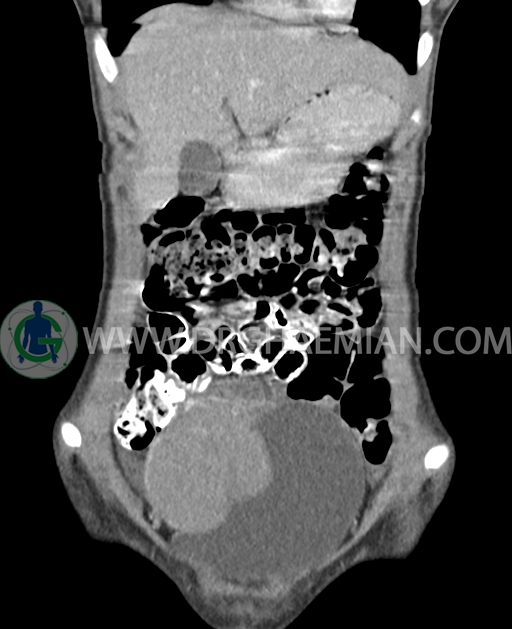

سی تی اسکن شکم و لگن از تشعشعات برای ایجاد تصاویر عرضی مقطعی از نایحه شکم و بین استخوان های لگن استفاده می کند. در این کیس تومور سلول زایا به ابعاد mm 125 x 112 x 80 دیده می شود.

در سی تی اسکن اسپیرال شکم و لگن با کنتراست خوراکی و وریدی (مولتی دیدکتور 16 با مقاطع ظریف و بازسازی های ساژیتال و کرونال) :

توده هیپردنس لوبوله بزرگ به ابعاد 125x112x80mm حاوی نواحی سیستیک داخلی و enhancement قابل توجه پریفرال همراه با آسیت متوسط در فضای شکم و لگن با احتمال بیشتر با منشا از تخمدان راست، درون لگن دیده می شود که در درجه اول مطرح کننده germ cell tumor می باشد .